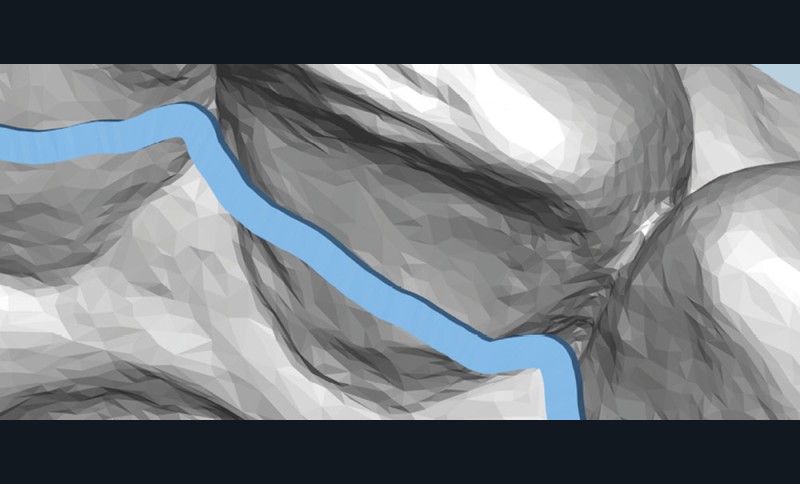

Dans le premier cas, il s’agit de plaques de nickel-titane usinées (fig. 10a-b) ou de fils de contention, pliés par un robot. Dans le deuxième cas, il s’agit de gouttières thermoformées sur des modèles (fig. 11), modifiés ou non, voire bientôt des gouttières imprimées directement.

Le début et milieu d’après-midi seront consacrés à l’empreinte numérique, désormais utilisée pour les empreintes d’étude, les set-up, le thermoformage. Les Drs Guillaume Lecocq et Stéphane Desplanques monteront le thermoformage et comment ces empreintes numériques peuvent permettre de confectionner des appareils vestibulaires, linguaux, voire des aligneurs (fig. 1 et 2).